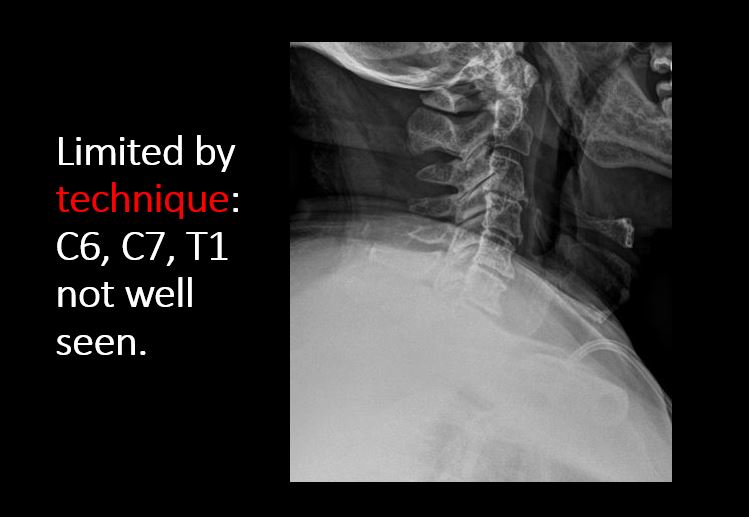

Technique

The craniocervical junction and/or C7-T1 are not entirely included on the exam.

The exam is over or under penetrated.

The exam is limited by overlying structures, bones or soft tissues, body habitus, patient positioning, support devices, or motion.